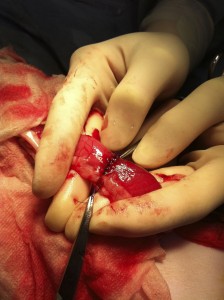

摘出した結石